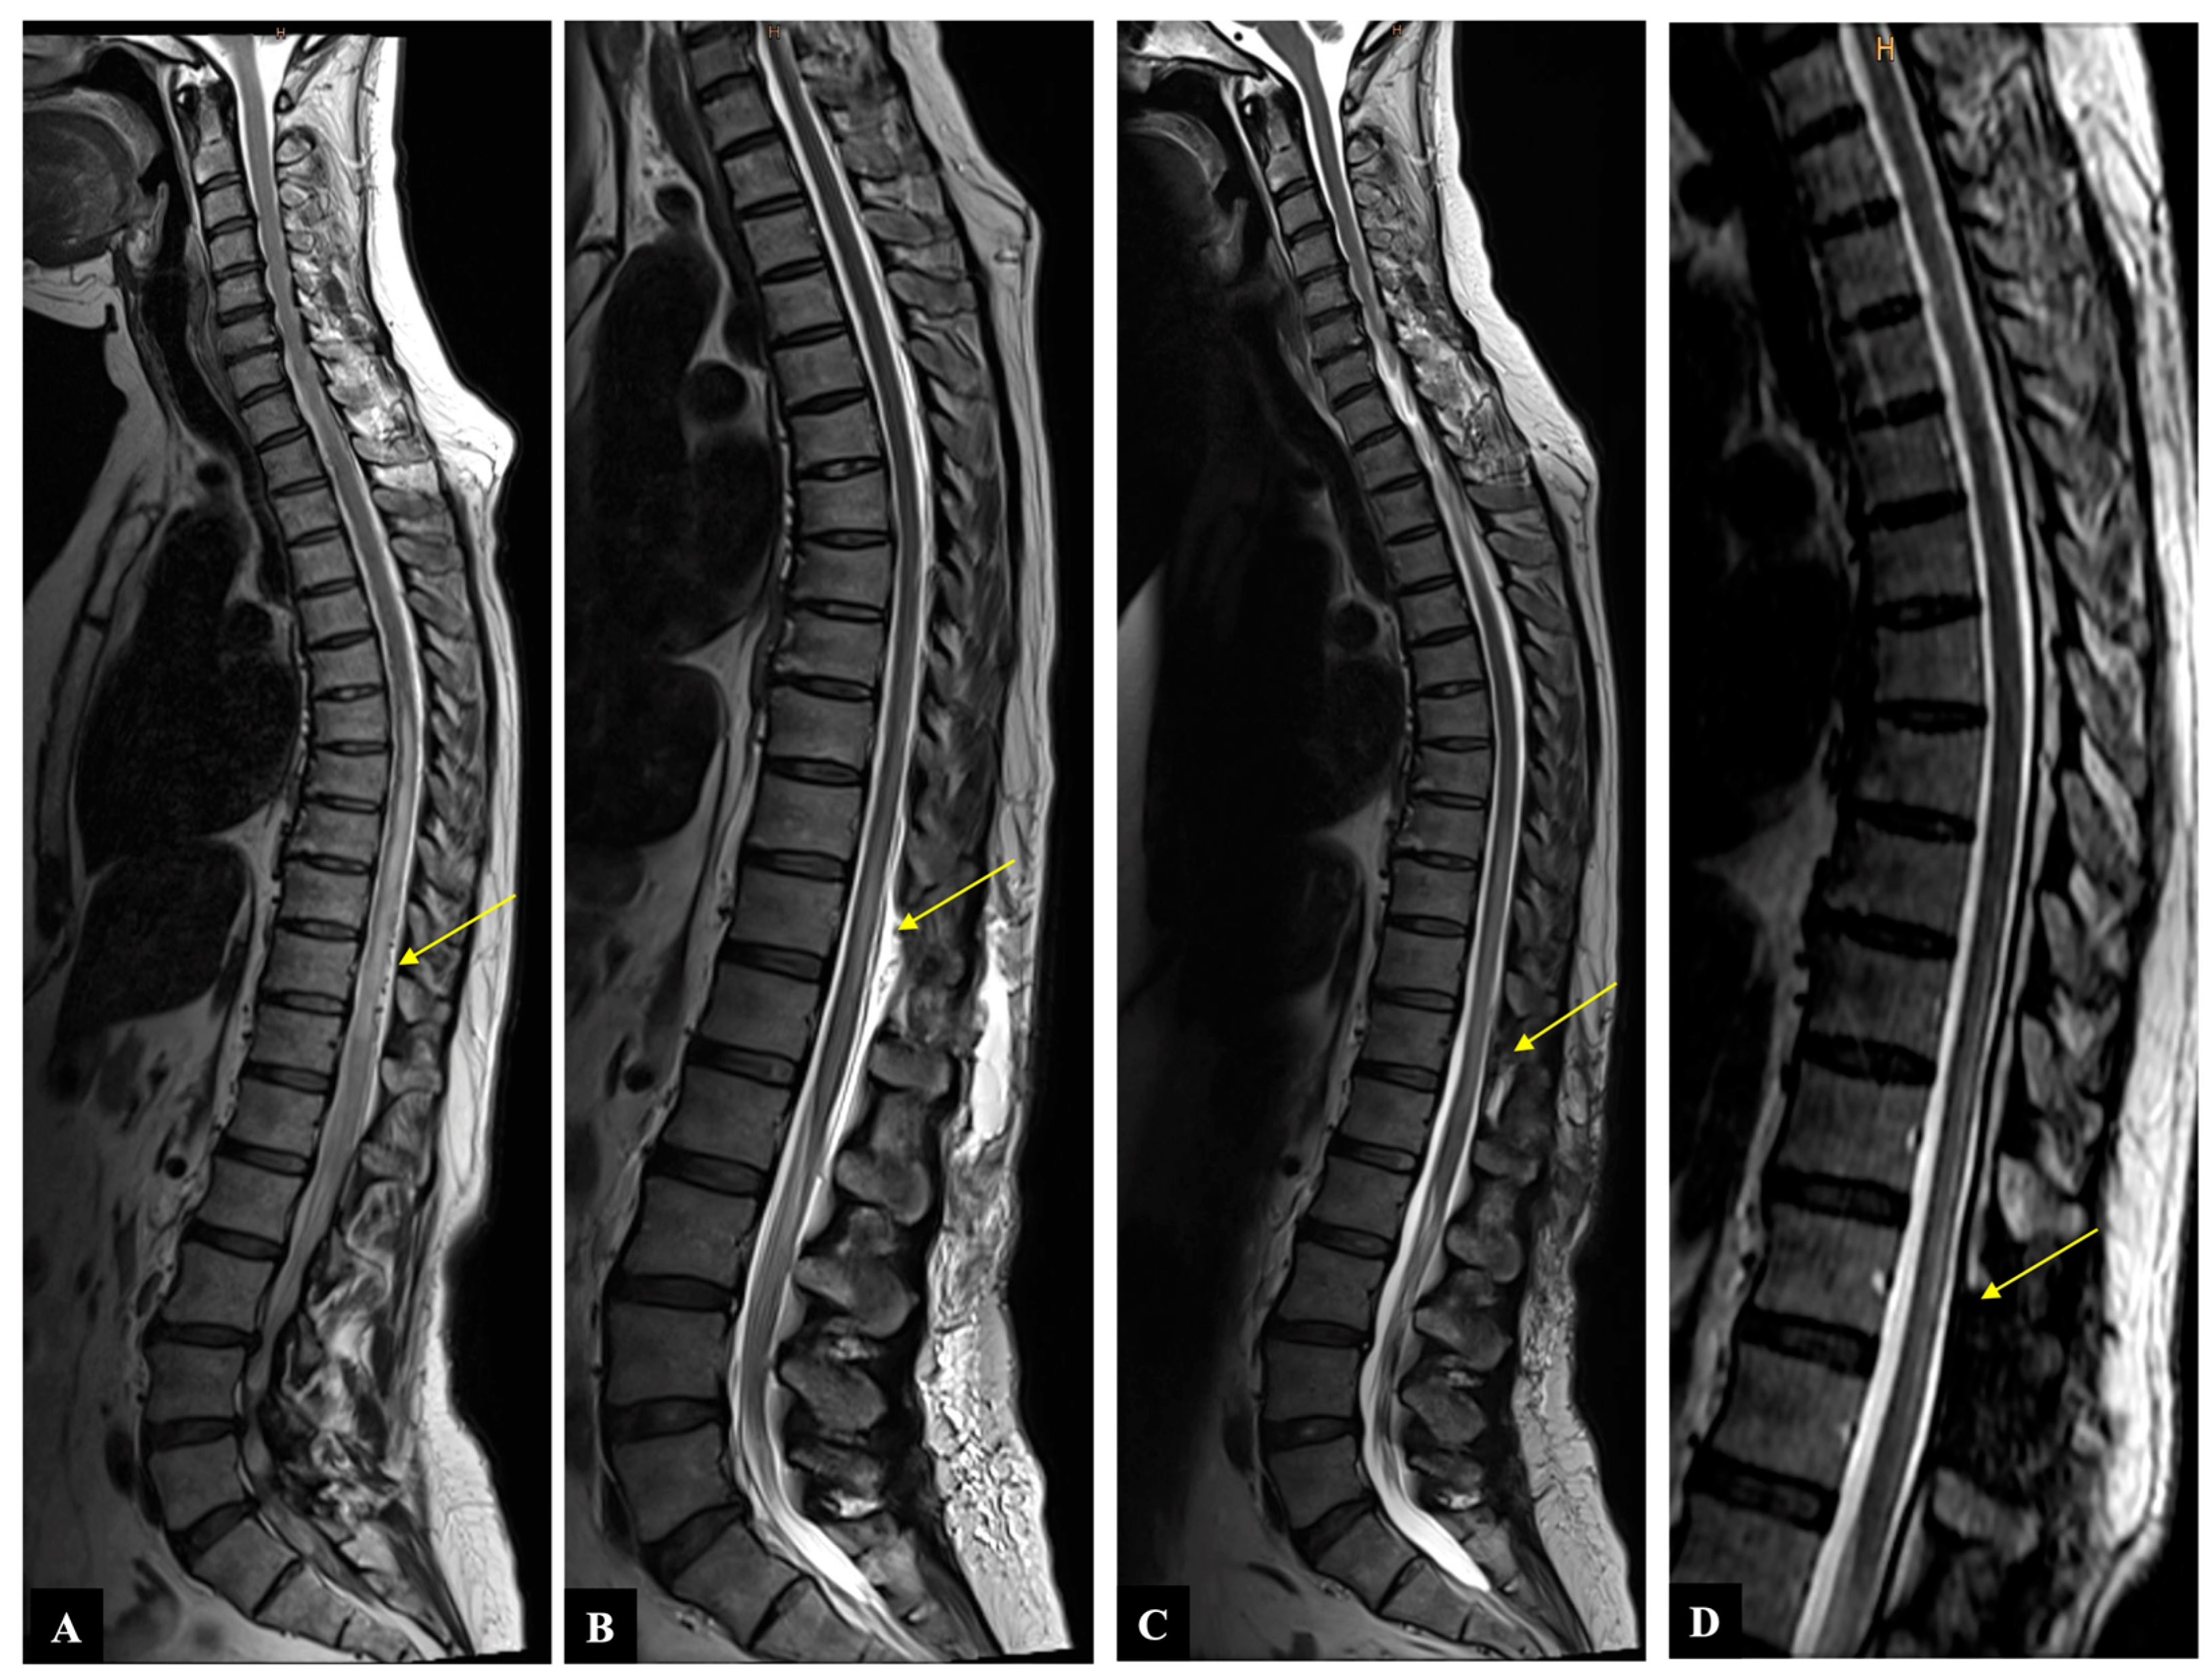

Figure 2. Case illustration: Sagittal T2-weighted MR image shows (A) preoperative spinal cord edema and flow voids (yellow arrow), (B) decrease in spinal cord edema and disappearance of flow voids immediately after operation (yellow arrow), (C) further decrease in spinal cord edema two months after operation (yellow arrow), (D) no myelopathy and no flow voids six months after operation (yellow arrow).

2.3. Illustrative Case

A 54-year-old woman presented with a one-month history of progressive gait disturbance, bowel and bladder dysfunction, and saddle anesthesia. The possible walking distance without a break was 200 m. There was also a slight paresis of the hip flexor and big toe extensor on the right side (ASIA-MS: 98, mALS: 6). The patient was admitted to the hospital by her general practitioner. On the day of admission, we performed a spinal MRI/MRA and DSA, which showed a DSAVF at the Th12/L1 level on the right. On the same day, the patient developed a rapidly progressing high-grade paraparesis with complete urinary and fecal incontinence (ASIA-MS: 70, mALS: 11). Emergency surgical treatment was performed via hemilaminectomy and closure of the right Th12 SDAVF without complications. Post-treatment DSA showed complete obliteration of the fistula, and MRI revealed no further flow voids and a reduction in myelopathy. The patient could be mobilized on the ward floor. After 2 months, the patient presented to the emergency room without motor deficits (ASIA-MS 100) but with a renewed deterioration of gait (gait score in mALS: 2) and persistent saddle anesthesia and leg paresthesia. The MRI showed further regression of the myelopathy and no signs of SDAVF recurrence. The gait disturbance improved spontaneously, and the patient was discharged home. At the second follow-up assessment (after 6 months), the MRI showed no myelopathy, but the patient still had a gait disturbance. A return to work was no longer possible. This case is the only one from our center with a rapid deterioration within one day, which we do not know in this form for this disease (Figure 2 and Figure 3).